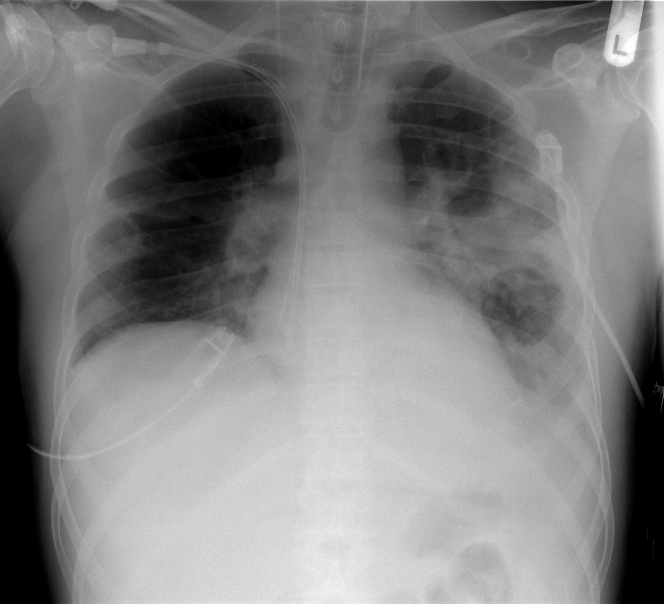

The role of chest radiography in confirming covid19 pneumonia The BMJ Do You Need A Chest Tube For Pneumonia A parapneumonic effusion refers to the accumulation of fluid in the pleural space in the setting of an adjacent pneumonia. If the fluid becomes infected, you may. If your pneumonia isn't clearing as quickly as expected, your doctor may recommend a chest ct scan to obtain a more detailed. Pneumonia may cause fluid to build up in the thin space. Do You Need A Chest Tube For Pneumonia.

Pneumonia Chest XRay MedSchool Do You Need A Chest Tube For Pneumonia If your pneumonia isn't clearing as quickly as expected, your doctor may recommend a chest ct scan to obtain a more detailed. If the fluid becomes infected as a result of pneumonia (called empyema), a chest tube (or, less commonly, surgery) may be. Chest tubes come in a variety of shapes and sizes. If the fluid becomes infected, you may.. Do You Need A Chest Tube For Pneumonia.